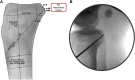

The posterior cruciate ligament (PCL) is known to be the main posterior stabilizer of the knee. Anatomic single-bundle PCL reconstruction, focusing on reconstruction of the larger anterolateral bundle, is the most commonly performed procedure. Because of the residual posterior and rotational tibial instability after the single-bundle procedure and the inability to restore the normal knee kinematics, an anatomic double-bundle PCL reconstruction has been proposed in an effort to re-create the native PCL footprint more closely and to restore normal knee kinematics. We detail our technique for an anatomic double-bundle PCL reconstruction using Achilles and anterior tibialis tendon allografts.